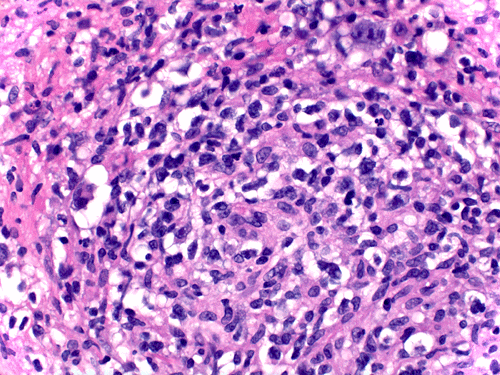

Histopathology: There is a necrotizing process with granulomatous reaction and perivascular lymphocytic infiltration. In some areas, there is concentric, perivascular lymphocytic infiltration surrounded by a granulomatous reaction (Panel A). On higher magnification, the lymphocytic infiltration appears to contain both small lymphocytes and scattered atypical cells with increased mitotic activity (Panel B and C). No definitive viral inclusion bodies are identified.

Special stains and Cultures: GMS stain, AFB stain, and immunohistochemistry for toxoplasma were negative. The large atypical cells were positive for CD20 (Panel D), and to a lesser extent CD30 and Epstein-Barr virus (EBV). Immunohistochemistry for CD68 highlighted numerous histiocytes, including those within vague granulomas. Numerous reactive T-cells were demonstrated by immunohistochemistry for CD45RO, CD2, CD3, CD5, CD7, and CD8, but not CD4.